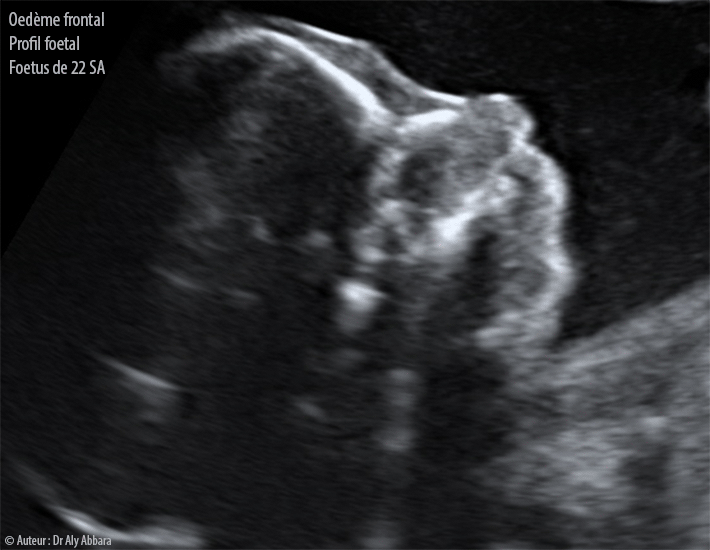

• Images échographiques au terme de 22 SA de grossesse montrant la présence d'un œdème frontal fœtal visible sur le profil facial.

• Cet œdème facial est associé chez ce fœtus par la présence d'un volumineux lymphangiome cervical droit étendu jusqu'à la région temporale homolatérale.

• Pas d'autres anomalies morphologiques associées.

• Clarté nucale à 12 SA est normale (1,3 mm) ; le risque combiné de trisomie 21 au premier trimestre est de 1/3000.

• Le caryotype fœtal est sans anomalie.